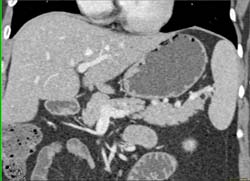

Insulinoma